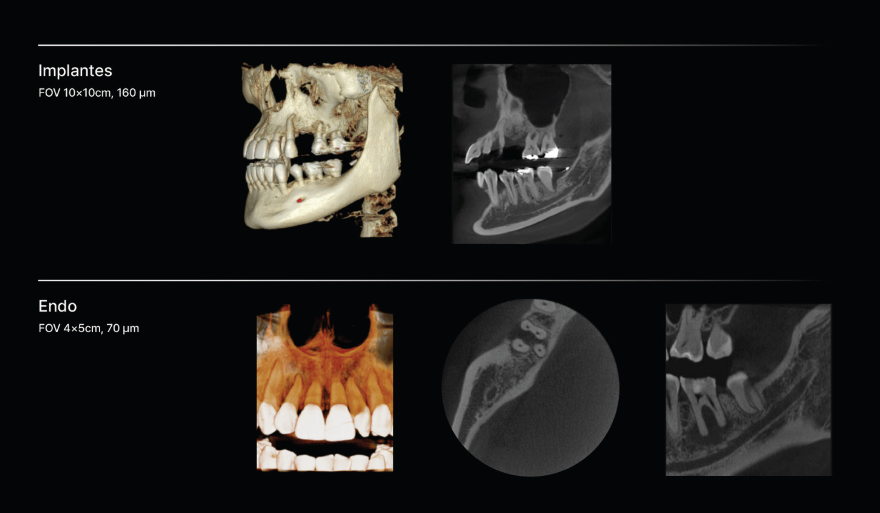

Imágenes de alta resolución para un diagnóstico preciso

Experimente una claridad de imagen excepcional y volúmenes de escaneo personalizables con RAYSCAN S. Adapte sus exploraciones para satisfacer sus necesidades clínicas específicas, asegurándose de capturar cada detalle intrincado y liberando posibilidades ilimitadas.

Diágnostico de todas las áreas

FOV 4 X 5 cm

70 μm

FOV (cm)

20 x 20

10 x 10

4 x 5

Tamaño de Vóxel (mm)

0.3

0.16

0.07